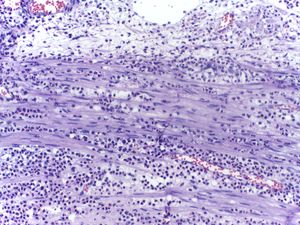

Micrograph showing several neutrophils during an acute inflammation